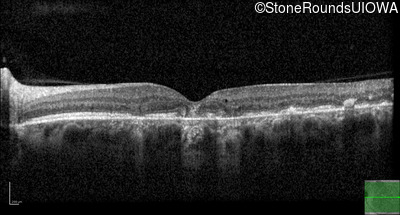

Age at visit: 49 years

This 49 year old man was first told he had a fundus abnormality on a routine eye exam at age 34. Ten years later he noticed some distortion just superior to fixation.

Pattern Dystrophy PRPH2 Gln239Stop CAG>TAG   AD